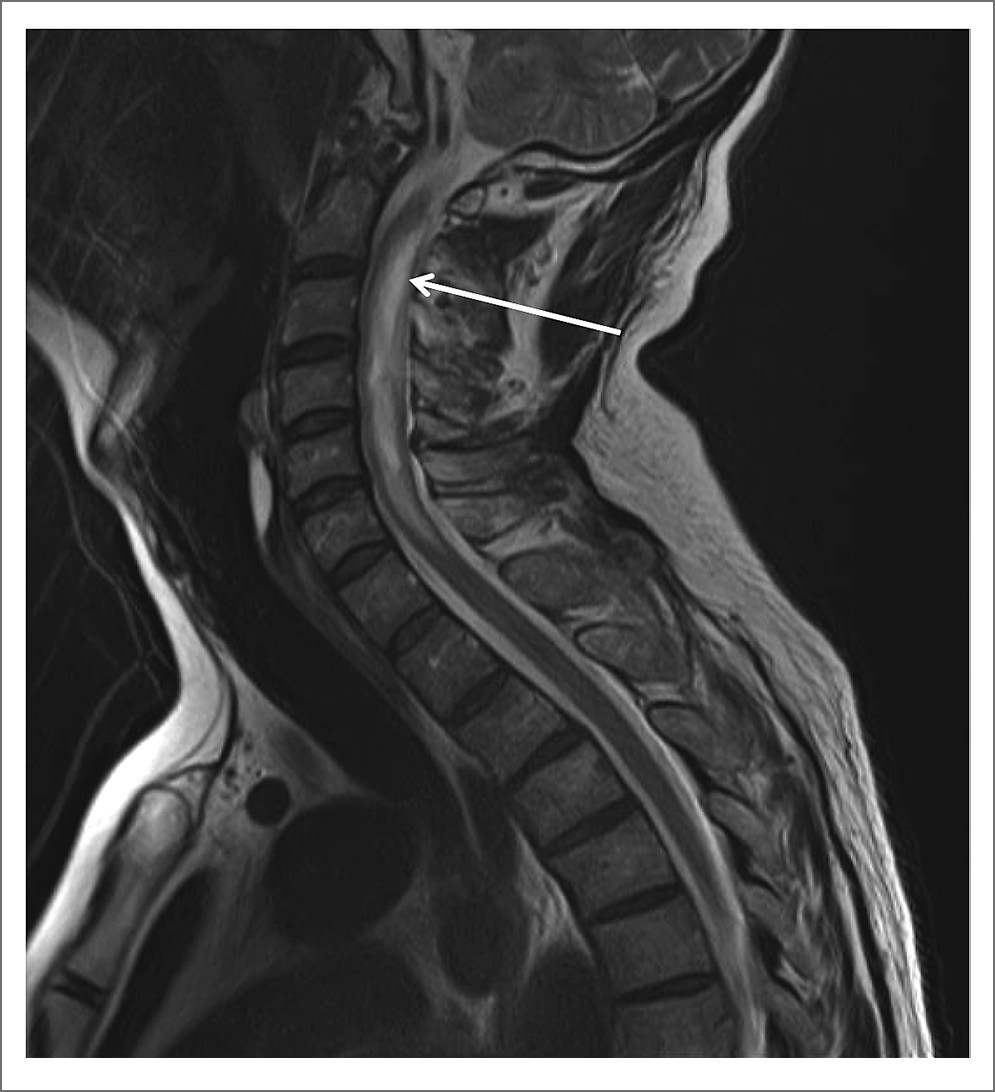

Для уточнения диагноза провели МРТ ГМ и спинного мозга. При исследовании ГМ отмечены единичные мелкие очаги в белом веществе и небольшие зоны лейкоареоза, отражающие микроангиопатию. МРТ-исследование спинного мозга в режимах T2-взвешенного изображения и FLAIR выявило протяженные участки повышенного МР-сигнала (на уровне шести шейных позвонков), заметное утолщение и неоднородную структуру шейного отдела спинного мозга, вероятно, воспалительного генеза (рис. 1, 2). При внутривенном контрастном усилении определялось накопление контрастного вещества в левом зрительном нерве на всем его протяжении (рис. 3) и в белом веществе спинного мозга, преимущественно в области задних столбов с переходом на нижнезадние отделы продолговатого мозга – зона аrea postrema (рис. 4).

Рис. 4 Накопление контрастного вещества в зоне патологических изменений в шейном отделе спинного мозга (показано стрелкой).

При динамическом МРТ-исследовании, проведенном через 3 нед на фоне продолжающейся глюкокортикостероидной терапии, сохранялось слабое накопление контрастного вещества по ходу левого зрительного нерва, отмечалось уменьшение толщины шейного отдела спинного мозга, на этом уровне стали прослеживаться субарахноидальные ликворные пространства, неоднородная структура спинного мозга в проекции СII–СV позвонков сохранялась, но протяженность зоны патологических изменений и накопления контрастного вещества существенно уменьшилась (рис. 5). Заключение: МР-картина воспалительных изменений в шейном отделе спинного мозга и зрительном нерве слева (признаки оптикомиелита).

Рис. 5 Уменьшение накопления контрастного вещества в шейном отделе спинного мозга на фоне терапии (показано стрелкой).